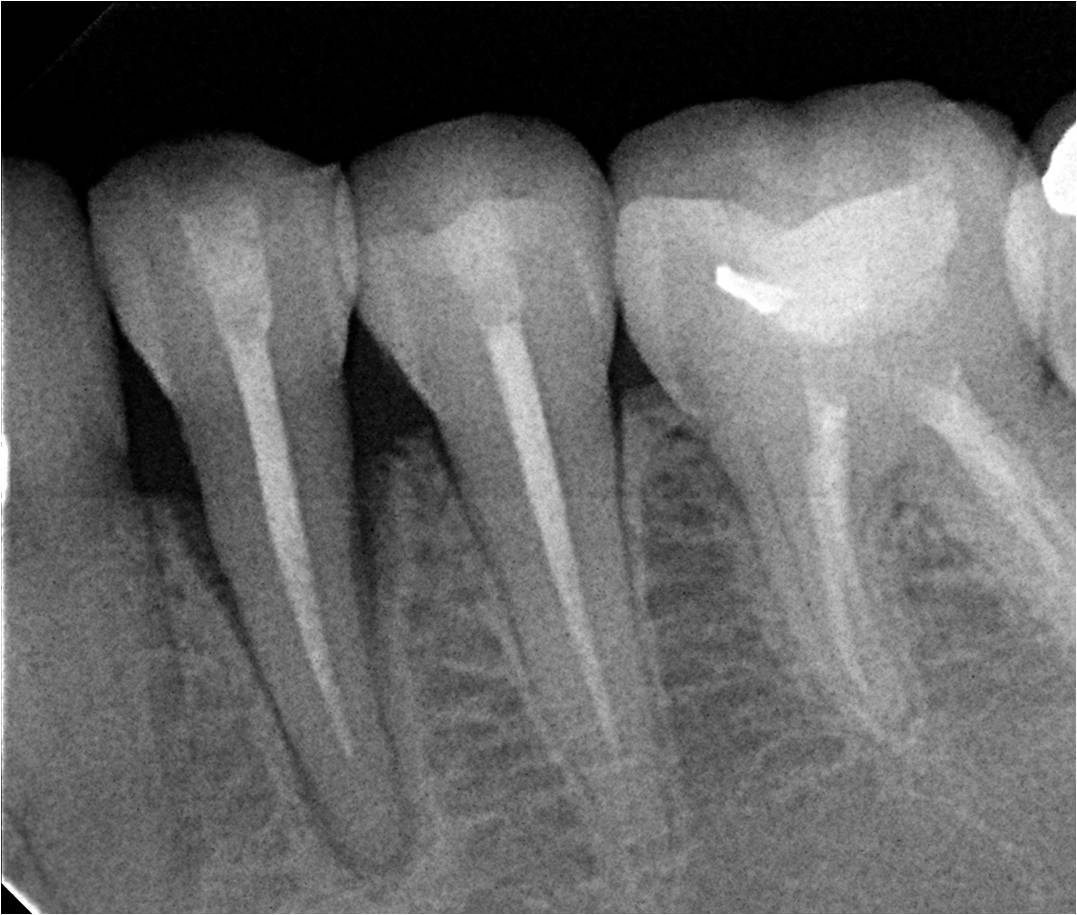

Methods: It was a case report of a 25 year old female patient who presented to dental clinic AKUH with the complaints of mobility in a tooth in lower left jaw. On clinical and radiographic examination her first premolar was periodontaly compromised and had a hopeless prognosis.An atraumatic tooth extraction was done under local anaesthesia and a Zimmer implant was immediately placed, primary stability achieved to 30Ncm. Temporary crown was placed on the implant on the same day using patient’s own pre extraction record. Her bite was adjusted to keep tooth slightly off occlusion.After a 2 weeks interval, excellent tissue healing was achieved and permanent crown was placed using cemented retention.